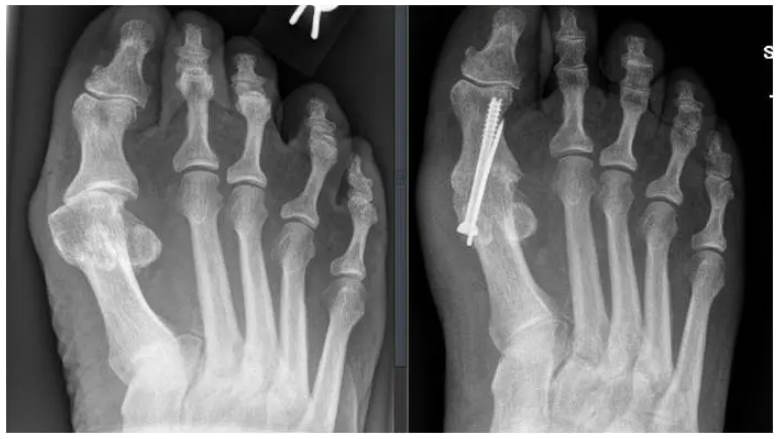

Arthrodese des Großzehengrundgelenkes:

Die Arthrodese (Versteifung) ist bei schweren und endgradigen degenerative Veränderung des Großzehengrundgelenkes mit entsprechender Beschwerdesymptomatik nach Ausreizung konservativer Maßnahmen indiziert. Aufgrund der guten postoperativen Ergebnisse wird sie als Goldstandard bezeichnet. Die Versteifung kann durch Schrauben, Platten bzw. Drähte erfolgen. Die Zehe wird bei Fehlstellung in achskorrigierter Stellung versteift. Der Vorteil der Arthrodese liegt in einer dauerhaften Therapie, bei der die meisten Patienten nach Ausheilung schmerzarm oder schmerzfrei sind. Ein hinkfreies Gangbild mit Abrollen über die Großzehe kann in der Regel durchgeführt werden.